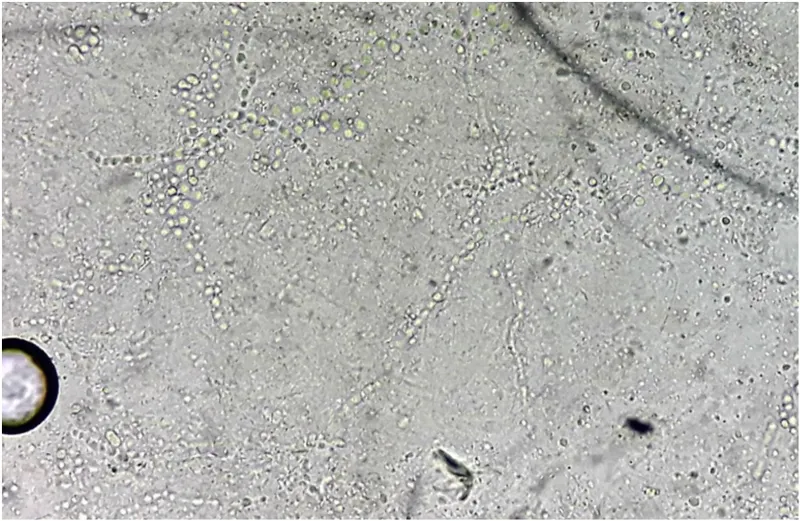

- Microscopy (KOH Mount):

- Reagent: 10-20% KOH (dissolves keratin).

- Visualizes: Septate hyaline hyphae, arthroconidia.

- Parker ink / Calcofluor white stain enhances visibility.

⭐ Arthroconidia are the infectious propagules formed by fragmentation of hyphae, characteristic of dermatophytes in tissue.